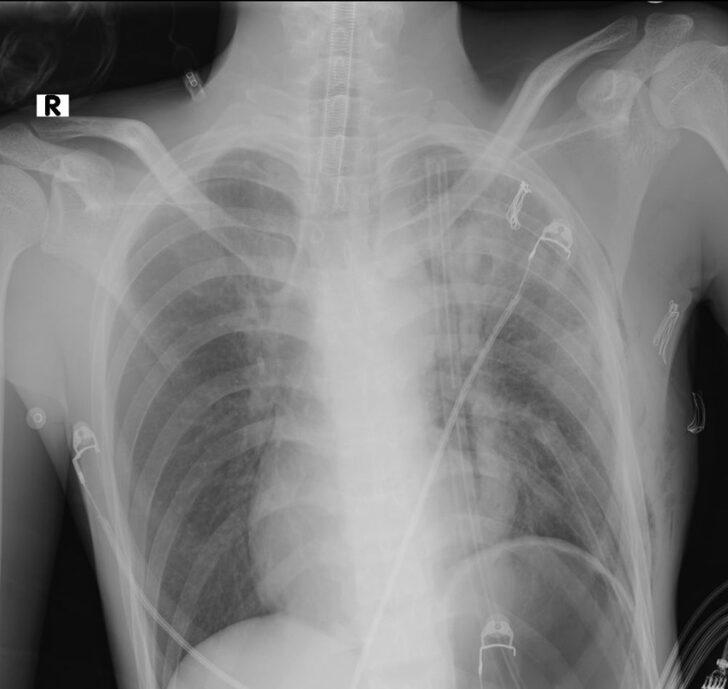

Tatil için ilçeye gelen 19 yaşındaki Endonezyalı I Made Pagehyasa Sangging, öksürdüğünde ağzından kan geldiği için Alanya Eğitim Araştırma Hastanesi'ne başvurdu. Muayene edilen Sangging'in sağ göğsünde kitle tespit edildi. Ameliyata alınan Endonezyalı hastanın göğüs kafesinden 3 kilogram ağırlığında ve 20 santimetre boyutunda bir kitle çıkarıldı.

Operasyonu gerçekleştiren Alanya Alaaddin Keykubat Üniversitesi (ALKÜ) Tıp Fakültesi Göğüs Cerrahisi Anabilim Dalı Başkanı Dr. Öğretim Üyesi Oktay Aslaner, gazetecilere yaptığı açıklamada, tetkiklerde kitlenin kalbe ve diğer organlara baskı yaptığını tespit ettiklerini söyledi.

Hastayı acil olarak ameliyata aldıklarını belirten Aslaner, sağ göğüs kafesinden iki akciğer arasında kalan 3 kilogram ağırlığındaki kitleyi aldıklarını ifade etti.

İlerleyen tıbbi cihazlar ve hastanedeki yoğun bakım olanakları ile ilerlemiş tümörlere müdahale edebildiklerini anlatan Aslaner, "Operasyonla hastanın akciğeri açıldı, kalbi rahatladı ve akciğer atar damarı normal hale geldi. Kitlenin tamamen çıkarılmasıyla hasta yeniden sağlığına kavuştu." dedi.